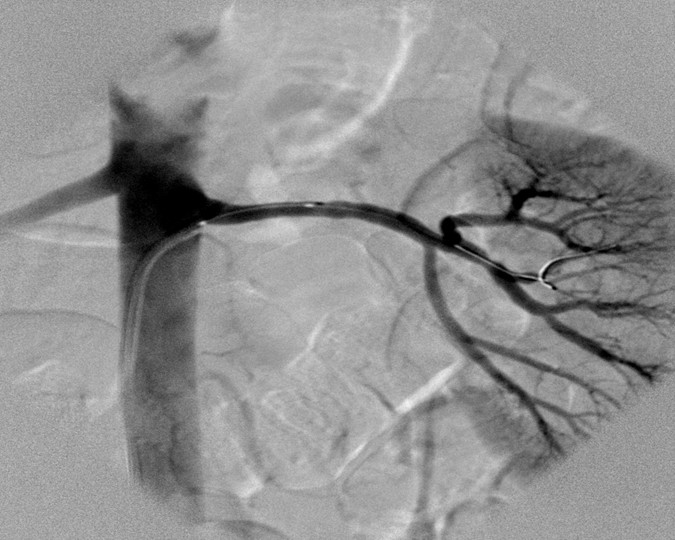

Angiografie einer Nierenarterienstenose aufgrund einer fibromuskulären Dysplasie Angiografie einer Nierenarterienstenose aufgrund einer fibromuskulären Dysplasie © wikipedia/Zeina AR, Vladimir W, Barmeir E. (CC2.0)